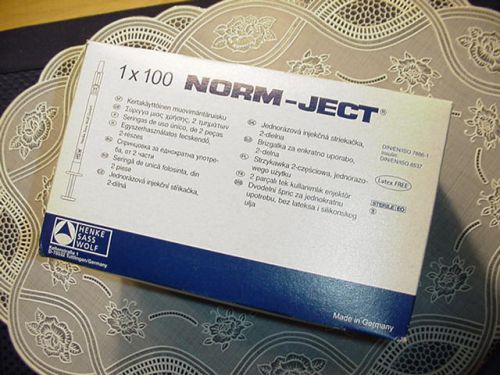

Norm-Ject Syringe 4020-000V0 2mL ( 3mL ) Luer Sterile Box of 100 Latex Free NEW

Norm-Ject 100 1 ML Tuberkulin Luer Disposable Syringes 4010.200V0 / Z230723-1Pak